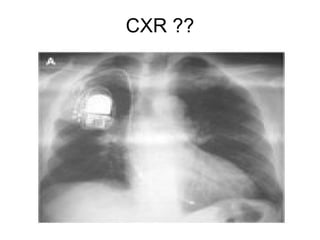

83 years old lady chronic AF , Dysphagia

An esophagogram obtained to evaluate dysphagia for solid food revealed a prominent impression of the left atrium on the esophagus , without evidence of obstruction.

CXR findings ?

Chest radiography (Panel A) revealed cardiomegaly (cardiothoracic ratio, 0.86), splaying of the carina, and an elevated left main bronchus (arrows). Plus PPM DDD

Echocardiogram showed massive biatrial enlargement (left larger than right),

An 83-year-old woman with long-standing atrial fibrillation who had previously undergone atrioventricular nodal ablation and pacemaker placement presented with symptoms of progressive heart failure. The patient was discharged home on medical management after prolonged diuresis.